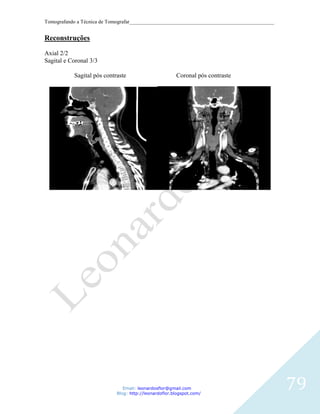

RECONSTRUCOES CORONAL, SAGITAL E 3D